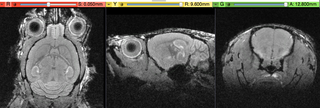

File:RegLib C41 RASoriented.png

Size of this preview: 800 × 270 pixels. Other resolutions: 320 × 108 pixels | 896 × 302 pixels.